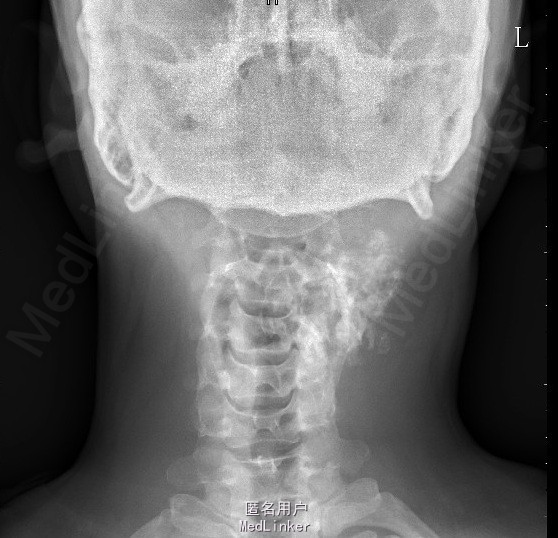

患者因“发现颈部包块5+年”入院。专科检查:左颈后见大小约5*6cm包块,质硬、边界欠清,无触痛。

辅助检查:颈椎正侧位片示:颈部左后份软组织内见多发片状稍高密度影,约C2、3椎体平面,与椎体附件结构分界不清,颈部MRI检查示:左颈后肌间隙肿块,大小约4.9*3.9*5.4cm,考虑肿瘤病变可能性大,其他待排。入院后积极完善相关检查,查CT示:约颈3-4平面左侧软组织内见类圆形混杂密度肿块影,最大截面约4.6x4.5 cm,内见多发不规则钙化灶,增强扫描见不均匀强化,局部与邻近附件骨质关系密切,局部皮质稍显毛糙,上述考虑肿瘤性病变可能